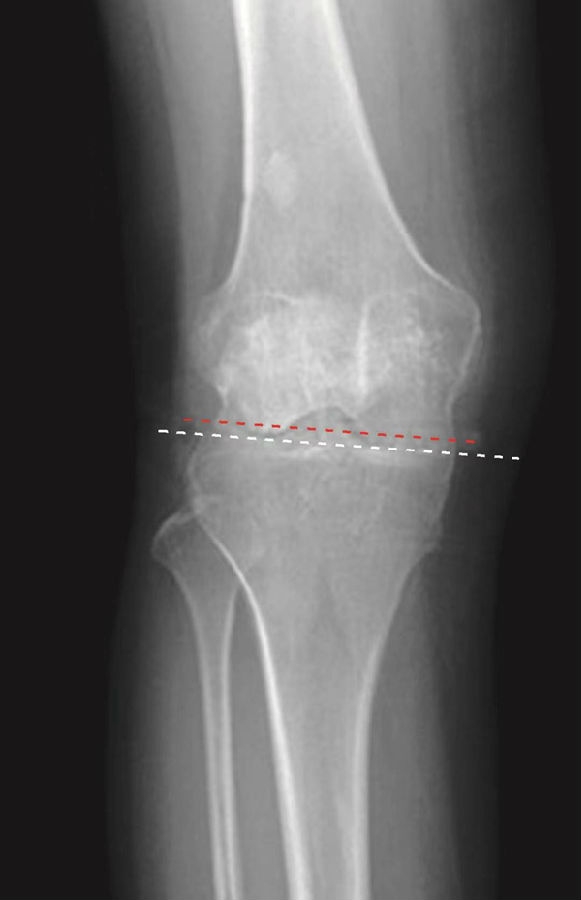

正常髌骨下极位于两侧股骨髁最低点连线之上,其下极在该连线近侧(图4)。髌骨高度大于其正常范围的最大值称为高位髌骨(图6),髌骨高度小于其正常范围的最小值称为低位髌骨(图5)。

图6 高位髌骨的正位X线片,髌骨下极过高地位于两侧股骨髁最低点连线之上